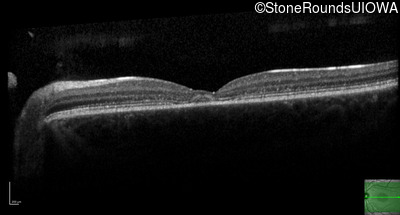

AR Stargardt Disease (IIA)

Age at visit:

16 years

OD

OS

20/40 -2

20/25

OCT Stack

AR Stargardt Disease

ABCA4

Gly607Arg GGG>AGG

Gly1961Glu GGA>GAA

AR